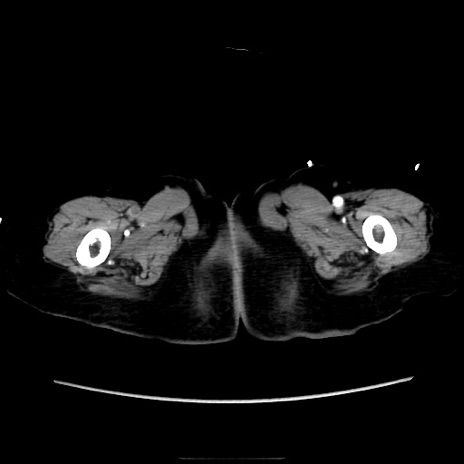

症例40(横断像)

【症例】90歳代女性

【主訴】腹痛・嘔吐

【現病歴】 食欲低下、嘔吐があり昨日他院受診。肺炎と診断され入院となる。入院後より腹部全体に圧痛あり。胃管留置され経過みていたが、症状持続するため、

当院転院となる。

【既往歴】胸椎圧迫骨折、胆石症

【身体所見】腹部:中央に激痛あり、圧痛あり、反跳痛不明

【データ】WBC 17100、CRP 18.82

他院CT

横断像